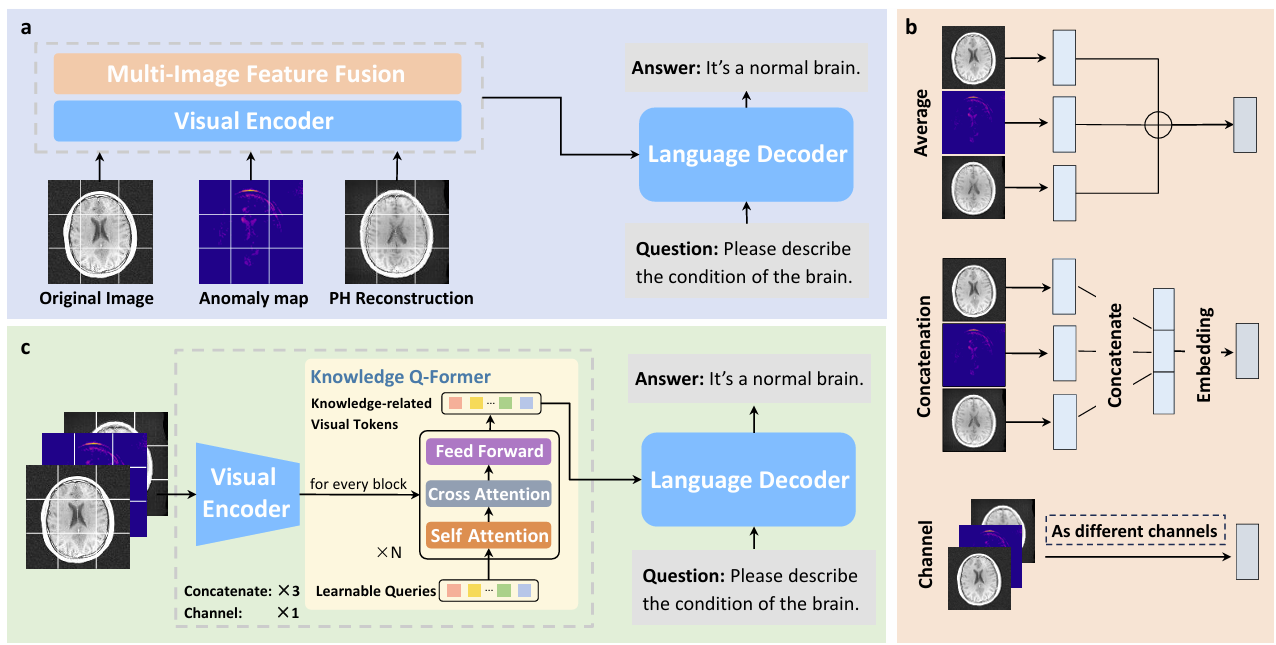

Jun Li, Che Liu, Wenjia Bai, Rossella Arcucci, Cosmin I. Bercea, Julia A. Schnabel.

[paper]

[project]

[huggingface]